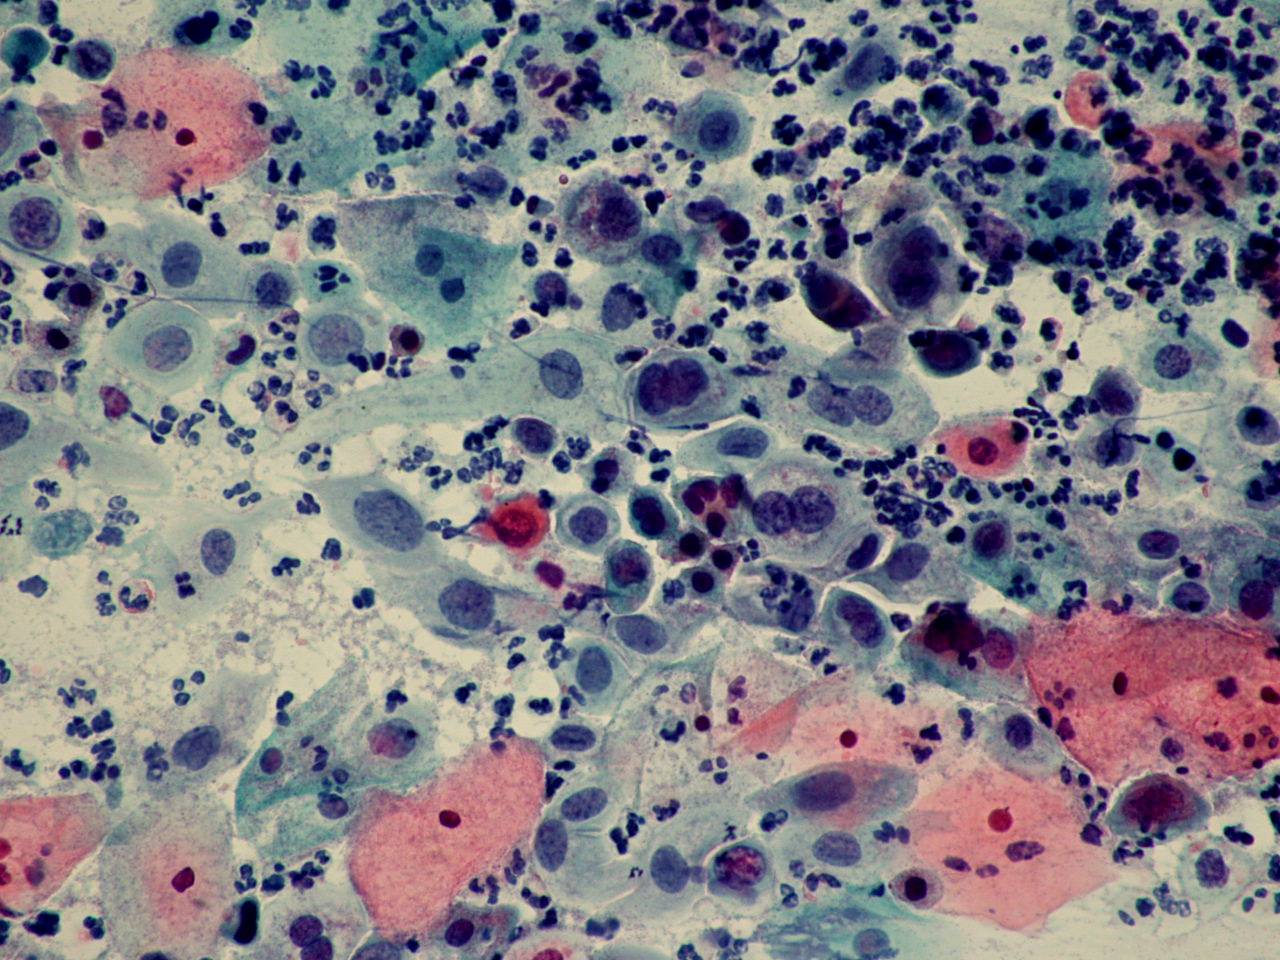

TBS-62.鳞癌

TBS-63.鳞癌

TBS-64.鳞癌

TBS-65.鳞癌

TBS-66.鳞癌